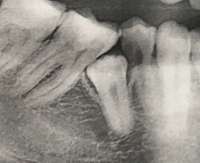

>>916336 (OP)Хочу поставить брекеты дистальный прикус Ортодонт отправил на снимок - обнаружили что нижние зубы мудрости расположены крайне хуёво один прорезался не полностью, другой почти не прорезался, расположены горизонтально, типа пикрил Сказал, что если хочу брекеты, то придётся их удалять. Офк ссусь. Какие подводные при удалении зубов мудрости? Насколько сильно мне может поплохеть после этого? Понимаю, что что-то конкретное сказать сложно, но врачиха-хирург в поликлинике нихуя мне толком не объяснила и вообще сука та ещё